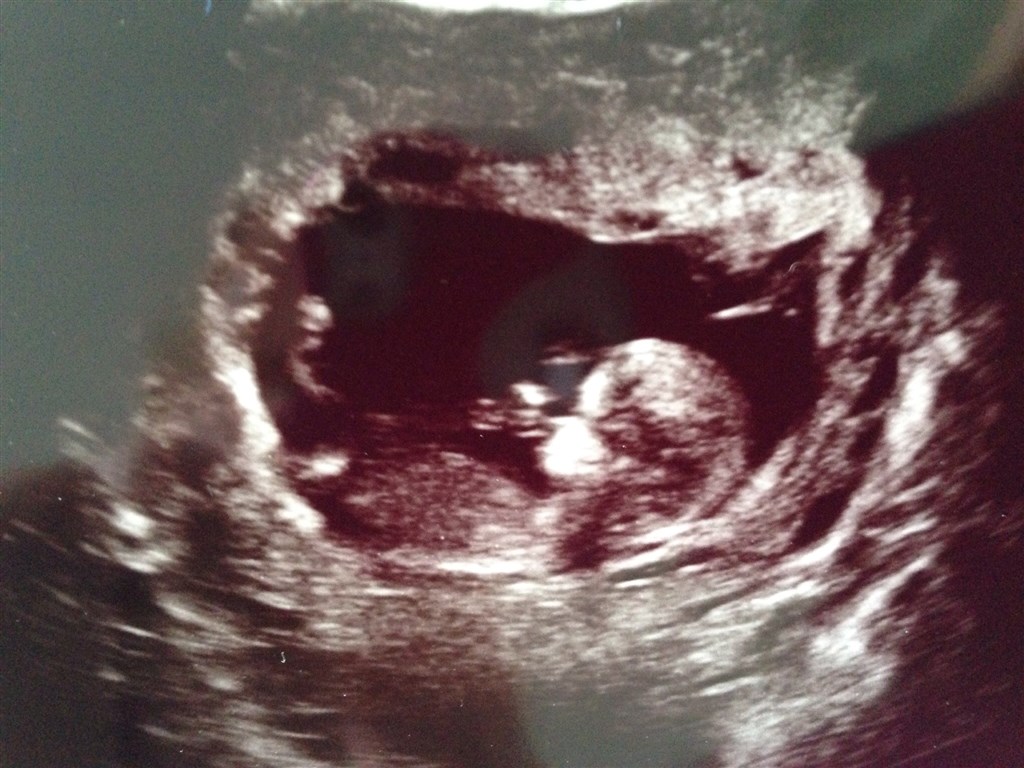

Nogle der vil gætte køn på baby?

Hvor langt henne er du da billedet blev taget? NF?

Og er det mon et ben eller en tap (som begge køn kan have tidligt) er er ved numsen? Eller navlesnoren eller..?

Hvis det er tappen man kan se, så vil jeg gætte på pige